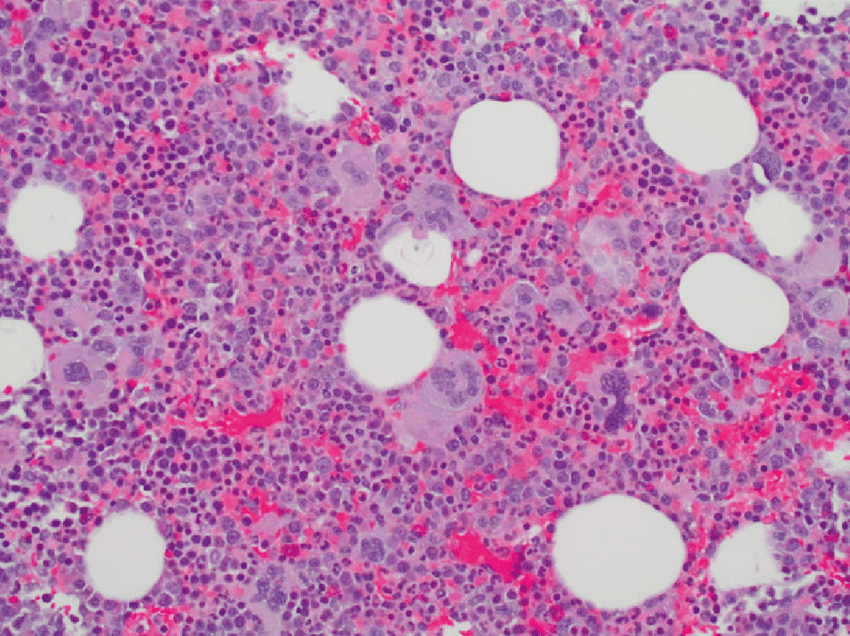

B. Rola szpiku kostnego w czerwienicy prawdziwej

Szpik kostny odgrywa kluczową rolę w produkcji komórek krwi, w tym czerwonych krwinek. W czerwienicy prawdziwej, szpik kostny jest miejscem, w którym nadmiernie namnażają się komórki macierzyste, co prowadzi do nadprodukcji czerwonych krwinek.

Ponadto, szpik kostny może być zastąpiony tkanką bliznowatą w wyniku rozwoju choroby, co dodatkowo utrudnia prawidłową produkcję krwinek. Dlatego też badania nad interakcją pomiędzy szpikiem kostnym a mutacjami genetycznymi mają kluczowe znaczenie dla zrozumienia mechanizmów choroby i opracowania bardziej skutecznych terapii.